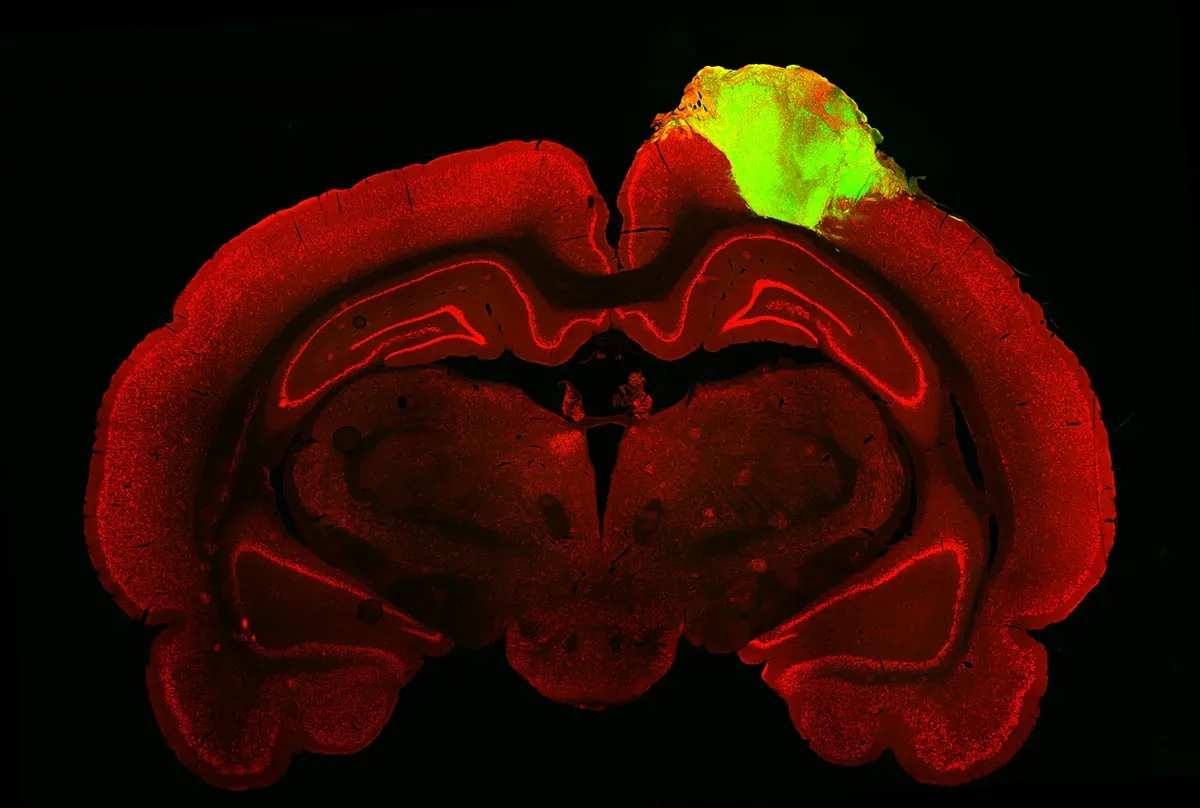

Учёные из Пенсильванского университета (США) провели смелый эксперимент и вживили взрослым крысам с повреждённой зрительной корой настоящие человеческие нейроны. Поскольку для опыта были нужны живые клетки, команда культивировала нейроны из стволовых клеток человека, которые росли в лаборатории 80 дней и сформировали ткань коры головного мозга.

Затем учёные удалили часть зрительной коры у 46 крыс, чтобы на освободившееся место перенести культивированные органоиды. Подопытных животных исследовали в течение трёх месяцев, и уже через два месяца человеческие органоиды начали формировать нейрональный ответ: пока крысам показывали изображения на экране, электрод считывал показатели органоидов.

Зелёным цветом показаны человеческие органоиды, а красным - остальной мозг крысы. Зелёным цветом показаны человеческие органоиды, а красным — остальной мозг крысы.© Jgamadze et al

В зависимости от типа картинки, — мигающие огни сменялись чёрными и белыми линиями, — человеческие нейроны тоже реагировали по-разному. А это означает, что органоиды полностью интегрировались в мозг крыс и взяли на себя некоторые функции зрительной системы зверьков. Кроме того, реакция подопытных животных оказалась такой же, как у здоровых крыс, хотя зверьки с органоидами хуже реагировали на свет.

Тем не менее, невзирая на такие поразительные успехи, исследователи так и не проверили главное  — улучшилось ли зрение крыс после трансплантации. Именно этот эксперимент запланирован следующим, в ходе которого учёные удалят другие части коры головного мозга крысы и заменят их органоидами. Если всё пройдёт успешно, такие органоиды можно будет пересаживать людям с травмами головного мозга, чтобы полностью излечивать паралич и другие тяжёлые состояния.